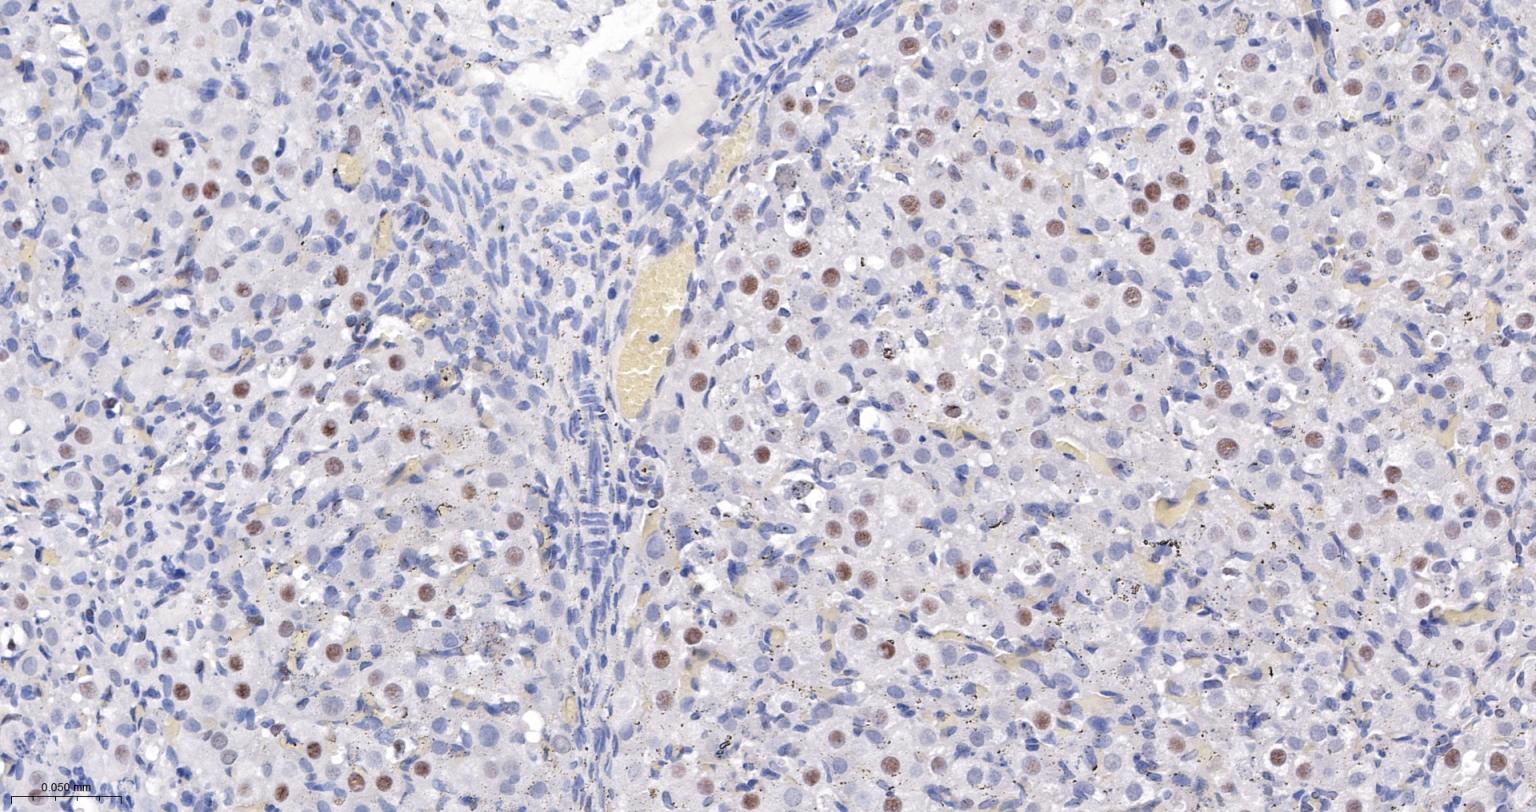

Paraformaldehyde-fixed, paraffin embedded Human Colon Cancer; Antigen retrieval by boiling in sodium citrate buffer (pH6.0) for 15 min; The section was incubated with USP39 Monoclonal Antibody, Unconjugated (bsm-63016R) at 1:200 overnight at 4°C, followed by conjugation to the bs-0295G-HRP and DAB (C-0010) staining.